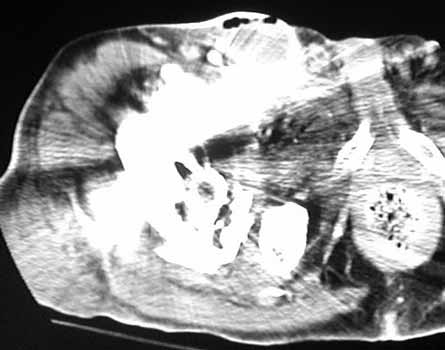

INFECTION—Soft tissue gas adjacent to dislocated cement spacer

INFECTION—Gas bubbles in synovial cyst anterior to right total hip replacement. Patient had infected left hip joint 1 year previously treated by Girdlestone procedure. Right total hip replacement was grossly loose and with migrated hardware.